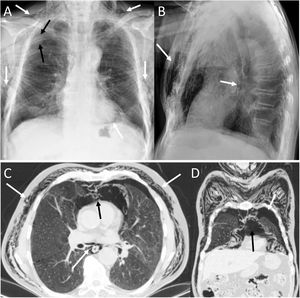

Spontaneous PM is not due to an apparent cause such as chest trauma. Rarely, it can be associated with pneumorrhachis, which is the presence of air in the spinal canal4 (Fig. 1). It is due to the passage of air from the submandibular and retropharyngeal spaces to the epidural space through the neural foramina.1 In general, this condition is benign and self-limited.1

A 63-year-old woman with dyspnoea. A) The chest X-ray (lateral projection) showed pneumomediastinum with air delimiting the anterior wall of the intrathoracic trachea and the cardiac silhouette (white arrows). B) The computed tomography also revealed the presence of air in the medullary canal (black arrows). Subsequent radiological studies showed resolution of the extrapulmonary thoracic air (not shown).

Tracheal rupture is rare, represents 15%–27% of all tracheobronchial lesions and is associated with high morbidity and mortality.7 The most common causes are chest trauma and orotracheal intubation (Fig. 2). Diagnosis can be delayed because the clinical and radiological findings are not specific, leading to complications such as failure of mechanical ventilation, mediastinitis, airway stenosis, bronchiectasis, recurrent infections and impaired lung function.7,8 Tracheal tears are frequently vertical and longitudinal and are located at the junction of the cartilaginous and membranous portions.8 The common and non-specific radiological findings are cervical subcutaneous emphysema and PM. If the cause is orotracheal intubation, a large dilatation and herniation of the endotracheal tube balloon outside the tracheal wall can be seen on computed tomography (CT) as a specific sign.7,8 Other signs would be the visualisation of the endotracheal tube outside the tracheal lumen, a focal defect in the tracheal wall and a deformity of the trachea.7 The CT enables the tracheal tear to be located in 70%–100% of cases, although the definitive diagnosis is made by bronchoscopy.8

A 36-year-old woman with attempted autolysis due to ingestion of benzodiazepines and acute respiratory failure, who presented with subcutaneous cervicofacial and thoracic emphysema after intubation. A) The chest X-ray revealed massive subcutaneous emphysema (white asterisks), hyperdistention of the endotracheal tube balloon (white arrows) and the distal end of the endotracheal tube in the proximal segment of the right main bronchus (black arrow). B) Computed tomography revealed pneumomediastinum with significant subcutaneous emphysema (black asterisks), bilateral pneumothorax (white asterisks) and hyperdistention of the endotracheal tube balloon with deformity of the posterior wall of the intrathoracic trachea (black arrow) due to post-intubation tracheal rupture. Treatment consisted of inserting two pleural drainage tubes for bilateral pneumothorax and selective intubation of the right main bronchus, with extubation at 36 h.